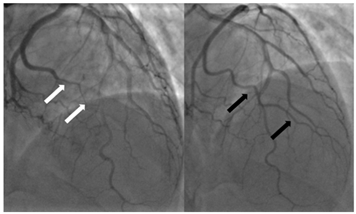

| Type 2b | Long, diffuse narrowing extending to the distal end without returning to normal calibre with no improvement following IC GTN | ![]() Type 2b SCAD of OM1 [initial angiogram white arrows]; repeat angiogram at 3 months with vessel healing [black arrows]. |